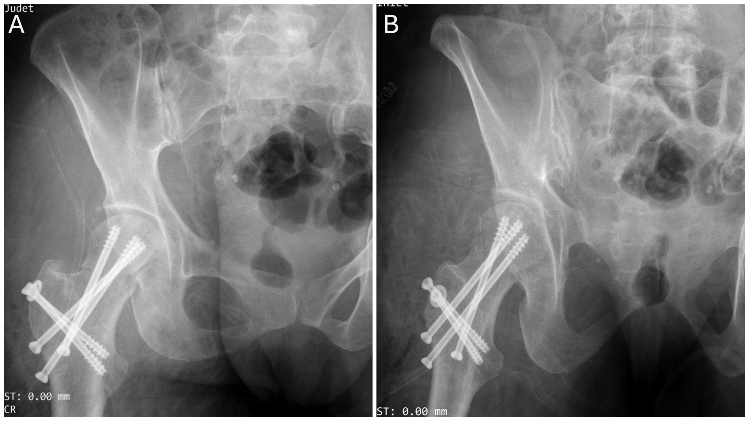

On the same day, considering the patient’s borderline age of 45–59 years, bone quality, and following a thorough discussion with the patient, a decision was made to proceed with osteosynthesis, and the patient was taken to the operating room. Under general anesthesia, the patient was positioned in the lateral decubitus position, and a modified Gibson approach was taken [13]. A trochanteric flip osteotomy was performed as described by Ganz et al. [14] to enhance visualization. A Z-shaped capsulotomy was then made to expose the femoral neck and proximal femur. The posterosuperior capsule, which was obstructing the reduction of the proximal femur, was incised under direct vision. The femoral neck fracture was then anatomically reduced and stabilized using cancellous cannulated screws inserted percutaneously under fluoroscopic guidance. Particular attention was paid to screw trajectory and placement to avoid compromising the femoral head fracture fragment. Following this, an anterior dislocation of the hip was performed, and the fractured segment of the femoral head was carefully retrieved from the acetabulum. Intraoperatively, the fractured segment of the femoral head was found to be infrafoveal, comminuted, and non-reconstructable. Therefore, excision of the fragment was performed. The hip’s range of motion was assessed and found to be stable. The anterior capsule was repaired, and the trochanteric osteotomy was fixed using two cancellous screws (Fig. 4). The wound was closed in layers. The patient withstood the surgery well, and the post-operative period was uneventful. The patient was mobilized with non-weight-bearing ambulation using a walker from post-operative day 1.

Figure 4: Image showing immediate post-operative X-ray (a) anteroposterior and (b) lateral view of right hip.